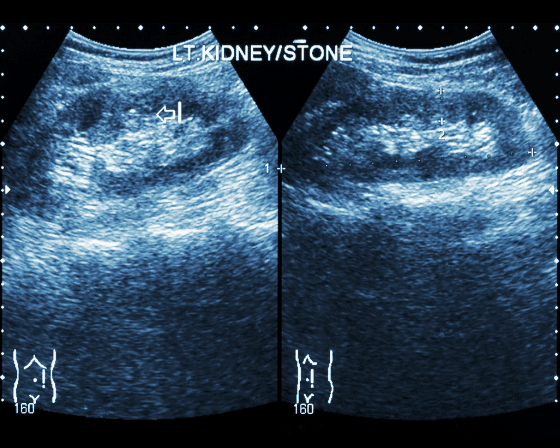

For diagnosis, specialized and general physicians would order a blood test, urine test, CT scan, or X-ray. For severe cases, multiple tests are applicable.

To note, the CT scan may include contrast dye usage. Patients with an issue with this component must inform the doctor beforehand for accurate preventive measures. Doctors usually conduct the evaluation and tests at the clinic. However, most treatments occur in the patients' homes or at the operating theatre.